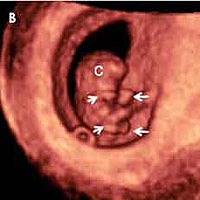

Al principio de esta semana, el bebé mide unos 4 a 5 milímetros y al final de la misma ha doblado con creces su longitud hasta tener una longitud cráneocaudal (LCC o medida desde la cabeza al coxis) de 1,2 centímetros, Se están desarrollando los intestinos, Están empezando a aparecer los vestigios de las piernas y los brazos, El embrión sigue teniendo una cabeza muy grande en comparación con el resto del cuerpo y una extremidad opuesta en forma de pequeña cola curvada.